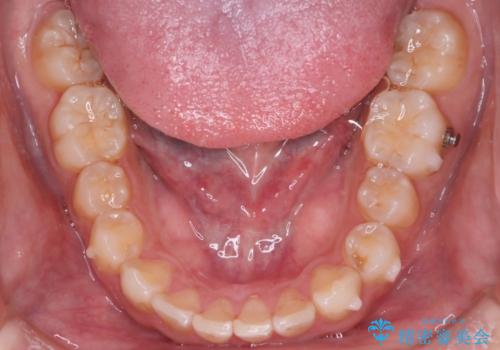

インビザラインにて治療を行うことで、前歯のがたつきが改善されました。

左上1番目の前歯はセラミックをご希望されたので、セラミックにて被せ物の治療を行いました。